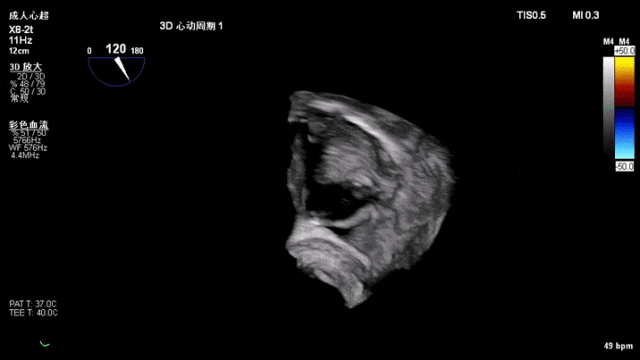

术中器械植入后3D